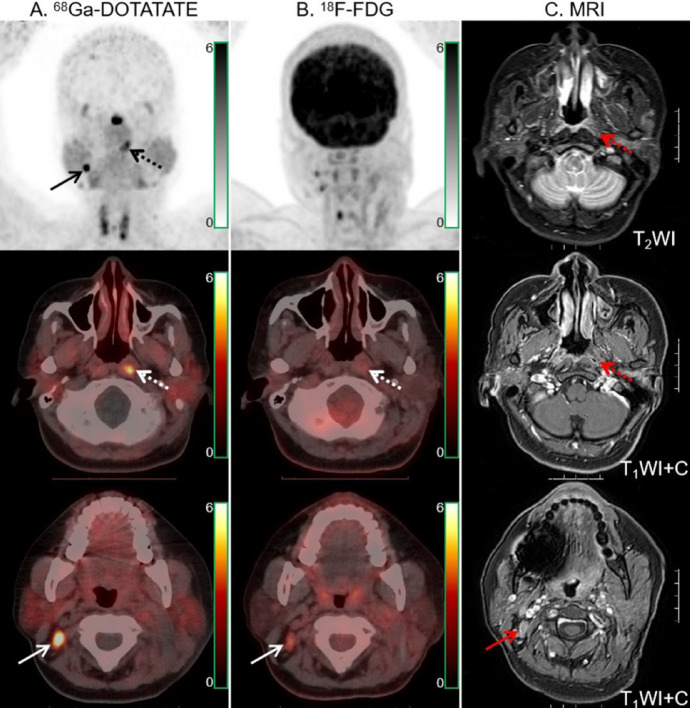

Fig. 3.

68Ga-DOTATATE (A) and 18F-FDG PET/CT (B) images in a 43-year-old man with NPC. Intense 68Ga-DOTATATE uptake was observed in the bilateral cavernous sinuses (dotted arrows), suggesting intracranial invasion, but 18F-FDG PET/CT revealed no abnormal intracranial 18F-FDG uptake (dotted arrows). Moreover, 68Ga-DOTATATE PET/CT showed strong tracer uptake in the sphenoid, occipital and petrous bones (solid arrow). The extent of skull base bone invasion (solid arrows) shown by 18F-FDG PET/CT was significantly smaller than that shown by 68Ga-DOTATATE PET/CT. MRI (C) findings were matched with 68Ga-DOTATATE PET/CT.

Table 2 compares lesion detection and radiotracer uptake between the two modalities. 68Ga-DOTATATE and 18F-FDG PET/CT had comparable primary tumor detection rates. In one newly diagnosed patient, 18F-FDG PET/CT and MRI were unable to identify the primary tumor (Fig. 1). One of the instances of primary tumor recurrence showed no positive radiotracer uptake on 68Ga-DOTATATE PET/CT 18F-FDG uptake was significantly higher in primary tumors than in 68Ga-DOTATATE. In 40 individuals, there was a moderate association between the two radiotracers’ absorption by the primary tumor (Fig. 2A). MRI revealed 27 cases of invasion of the skull base bone and 11 occurrences of intracranial invasion. 68Ga-DOTATATE PET/CT detected more skull base bone invasion (100% [27/27] vs. 96.3% [26/27]) and intracranial invasion (100% [11/11] vs. 54.5% [6/11]) than 18F-FDG. Compared to 18F-FDG, 68Ga-DOTATATE PET/CT revealed a larger lesion area in two invasions of the skull base bone and three intracranial invasions. The example in Fig. 3 demonstrated how the two approaches differed in determining primary tumor invasion.